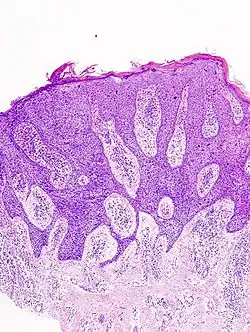

Der Morbus Bowen, auch: Dermatosis praecancerosa Bowen, Erythroplasie de Queyrat (s. u.), Dyskeratosis maligna, ist ein intraepidermales Carcinoma in situ. Dies bedeutet, dass sich die Hautzellen zwar bereits bösartig verändert haben, aber die wichtige Trennschicht Basalmembran noch nicht durchbrochen haben. Erst unterhalb der Basalmembran gibt es in der Haut Blut- und Lymphgefäße. Die bösartig (=maligne) veränderten Zellen des Morbus Bowen können daher nicht metastasieren, da sie keinen Gefäßanschluss haben. Es handelt sich daher beim Morbus Bowen um eine Hautkrebsvorstufe, noch nicht um einen echten Hautkrebs. Nach Monaten bis Jahren kann aus einem Morbus Bowen ein bösartiger Tumor, in diesem Fall ein kutanes Plattenepithelkarzinom (früher Spinaliom, Stachelzellkrebs) entstehen. Ein Plattenepithelkarzinom, das aus einem Morbus Bowen entstanden ist, bezeichnet man als Bowen-Karzinom. Die Veränderungen der DNA der Hautzellen, die zur Entstehung eines Morbus Bowen führen, können durch Sonnenlicht, chemische Stoffe (Arsen) und bestimmte Viren (HPV) ausgelöst werden. Die Erkrankung ist nach John T. Bowen benannt, der sie zuerst beschrieb. Der Morbus Bowen ist eine Erkrankung der zweiten Lebenshälfte und tritt etwas häufiger bei Männern als bei Frauen auf. Neben der Aktinischen Keratose ist er eine weitere wichtige Präkanzerose der Haut.

Die Diagnose wird in der Regel aufgrund feingeweblicher Untersuchung gestellt. In der verbreiterten Epidermis finden sich atypische, zu Einzelverhornung neigende Zellen. Die Basalmembran ist intakt (ansonsten muss man bereits von einem Karzinom ausgehen).